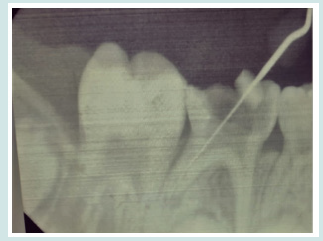

A girl child of 6 years had come to the department of pedodontic and preventive dentistry at the dental institution with a chief complaint of pain in the in the lower left back tooth region of jaw since past one week. On clinical examination she was having deep occlusal caries with respect to tooth number 85. Radiographically, the caries had progressed to the pulp chamber. The presence of third root/ additional root was also revealed. The diagnosis of chronic irreversible pulpitis with 85 was made (Figure 1). It was also found through radiograph that extra root was present with respect to 84 and 75 which were healthy. The tooth was isolated and access opening was done under local anesthetia and all the canals were located. Those were mesiobuccal, mesiolimgual, distobuccal and distolingual with the working length of 15mm in all the four canals (Figure 2). Cleaning and shaping of all the canals were done. Followed by obturation with metapex (Figure 3). The cavity was then sealed with permanent restorative material followed by stainless steel crown cementation.